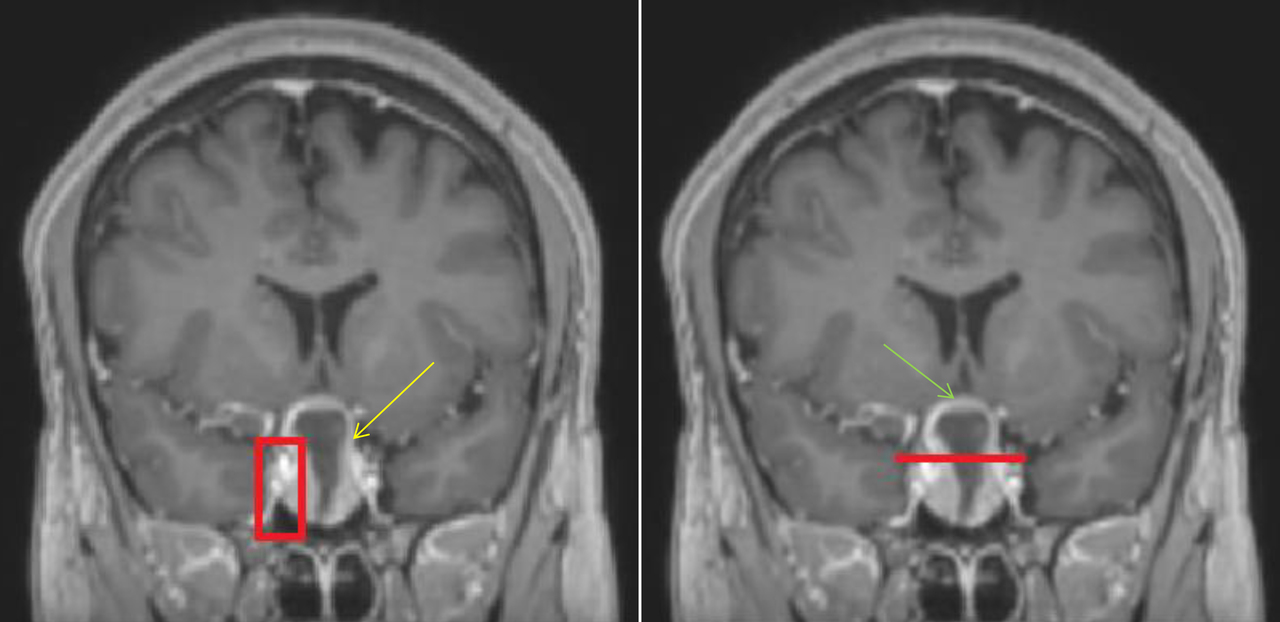

Le patient bénéficie également d’une imagerie par résonance magnétique (IRM) cérébrale devant un doute sur le scanner. Voici deux coupes (figures 2 et 3) :

Figure 2 (source : G. Kielwasser)

Sur la coupe coronale d’IRM en séquence T1 avec injection de gadolinium ci-dessous (figure 2 bis), on constate :

– sur l’image de gauche, que les sinus caverneux sont visibles de part et d’autre de la fosse pituitaire avec les vaisseaux rehaussés par le gadolinium. La flèche jaune pointe la masse hétérogène (centre hyposignal, périphérie hypersignal), en lien avec l’apoplexie pituitaire qui correspond à une hémorragie au sein du macro-adénome hypophysaire ;

– sur l’image de droite, que la ligne rouge correspond à une limite approximative de la loge pituitaire que l’hypophyse ne devrait pas dépasser. La flèche verte pointe le chiasma optique comprimé par la masse.